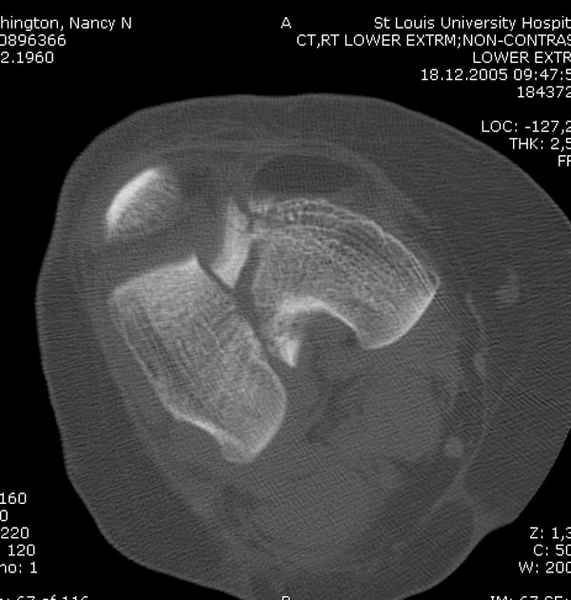

Имя     : distal femur ct.jpg

Тип     : image/jpeg

Размер  : 36739 байтов

Описание: отсутствует

Url     : http://weborto.net:8080/pipermail/ortho/attachments/20081001/5646c87e/attachment-0016.jpg